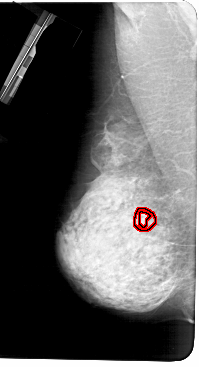

A_1282_1.LEFT_MLO

LEFT_MLO LINES 5491 PIXELS_PER_LINE 2971 BITS_PER_PIXEL 12 RESOLUTION 43.5 OVERLAY

FILE: A_1282_1.LEFT_MLO.OVERLAY

TOTAL_ABNORMALITIES 1

ABNORMALITY 1

LESION_TYPE MASS SHAPE ARCHITECTURAL_DISTORTION MARGINS SPICULATED

ASSESSMENT 4

SUBTLETY 1

PATHOLOGY BENIGN

TOTAL_OUTLINES 2